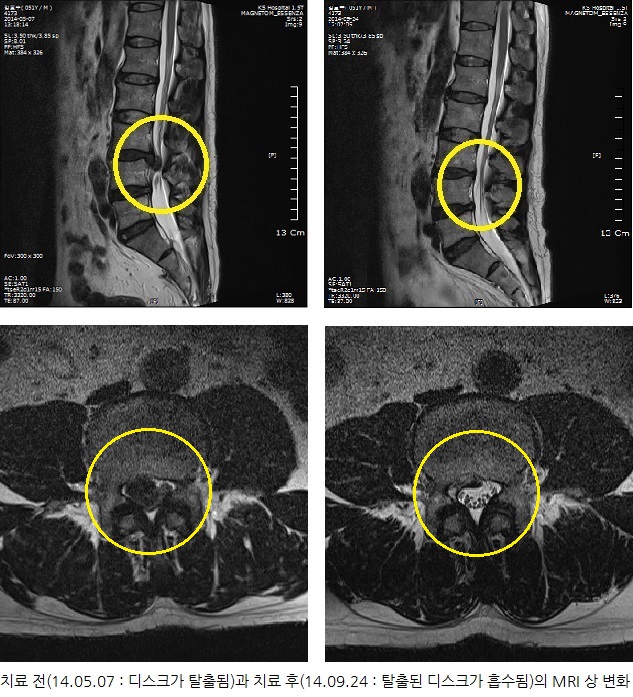

치료전후 MRI 비교